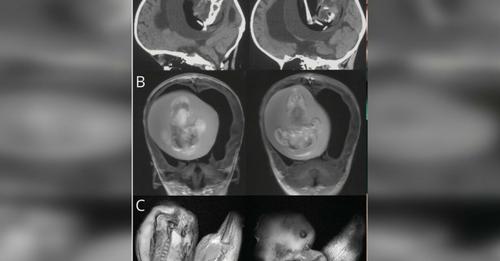

Lábcsontjai, felső végtagjai és ujjszerű…